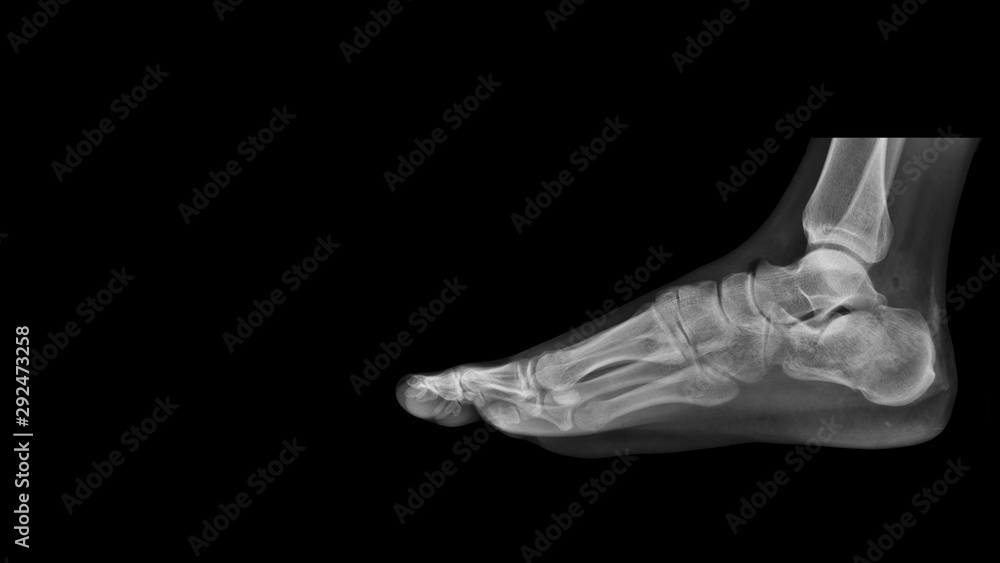

One involves the subtalar joint and one does not involve the joint. It generally takes six to eight weeks to walk after a calcaneal fracture. A calcaneus fracture is a broken heel bone.

Most will need to wait 3 months. Fractures or breaks of the calcaneus commonly occur after a fall from a height or car accident. Treatment of these fractures may require surgery.

How long does it take to walk after a calcaneal fracture. A minor fracture allows you to walk after 68 weeks of immobilisation in a non-weightbearing cast. This time frame may be shorter or longer depending on the severity of the fracture and the individuals.

Heel Fracture Symptoms To Watch For. The broken bone will take 3-4 months to heal with or without surgery.